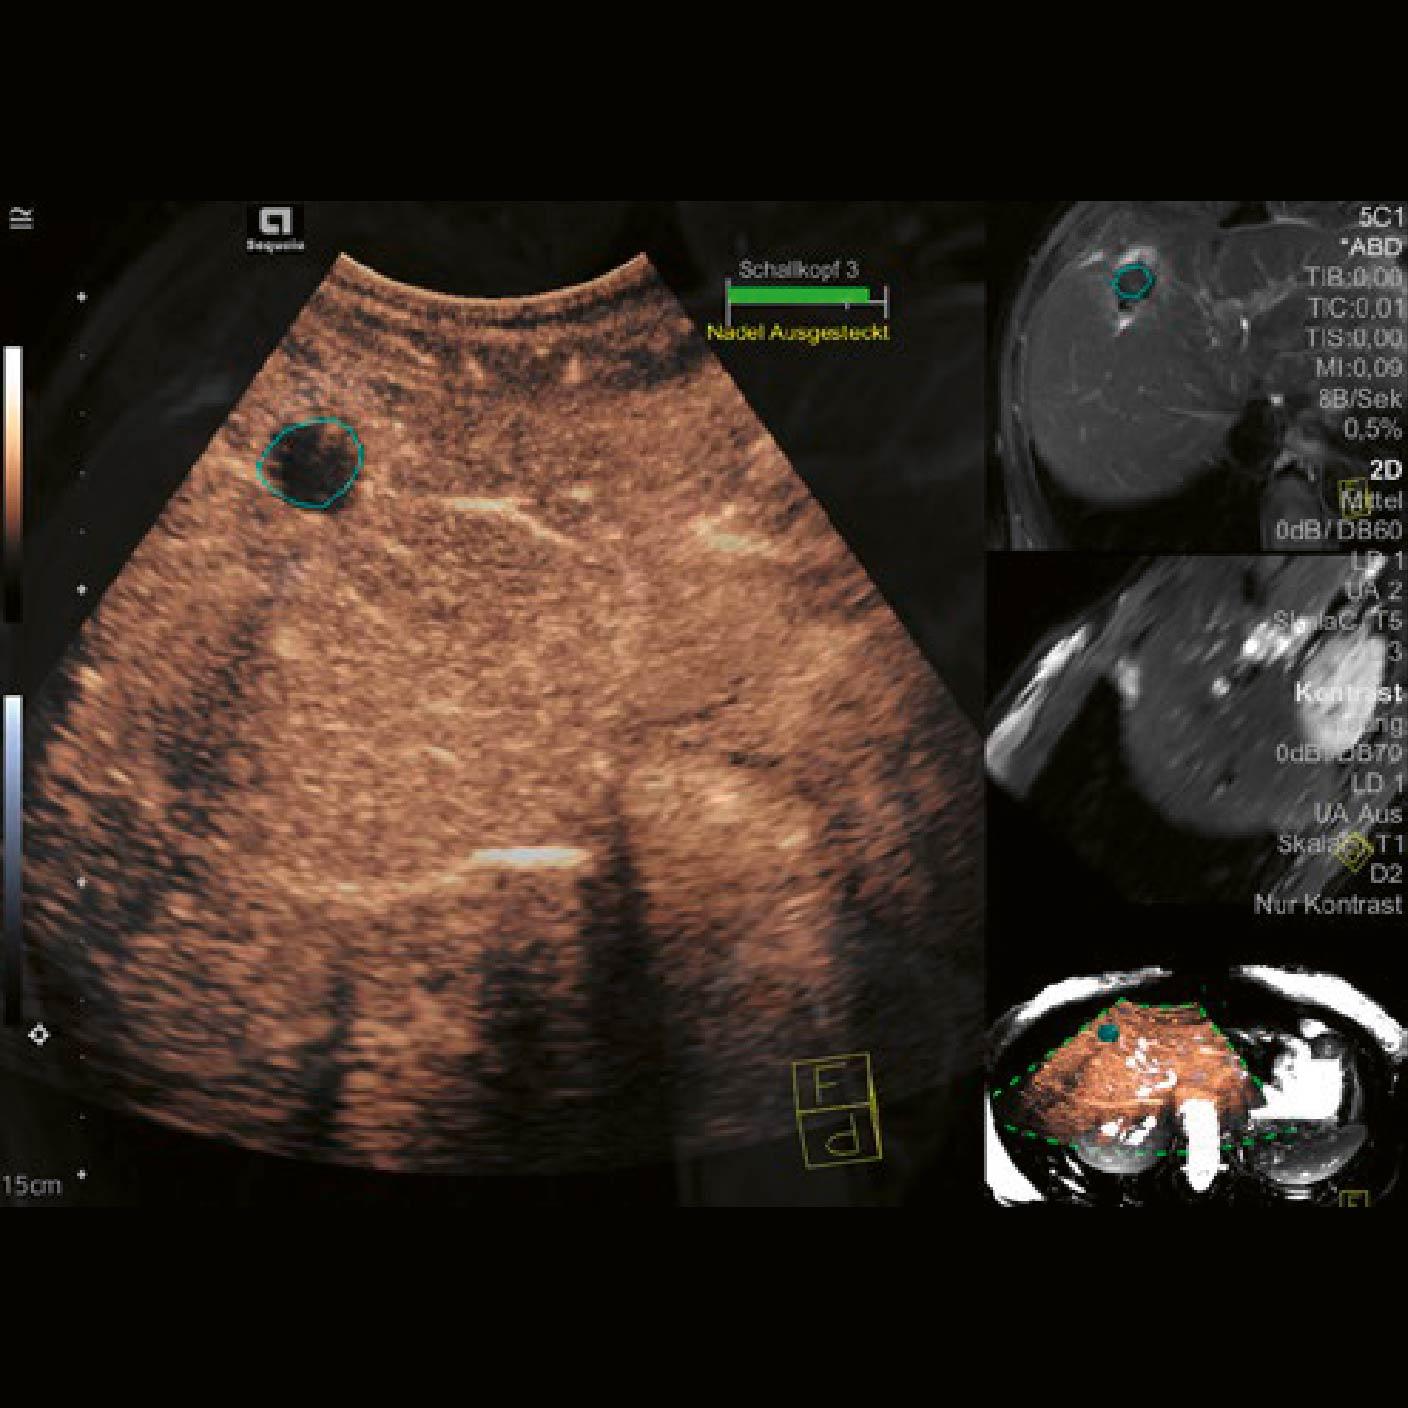

La administración de microburbujas como agente de contraste mostró que el área tratada era hipoecoica en la fase arterial [Fig. 3], característica que se mantuvo en la fase portal [Fig. 4]. Basándose en las características hipo-realzadas de la ROI observadas con CEUS, se concluyó que no había nuevas lesiones presentes.